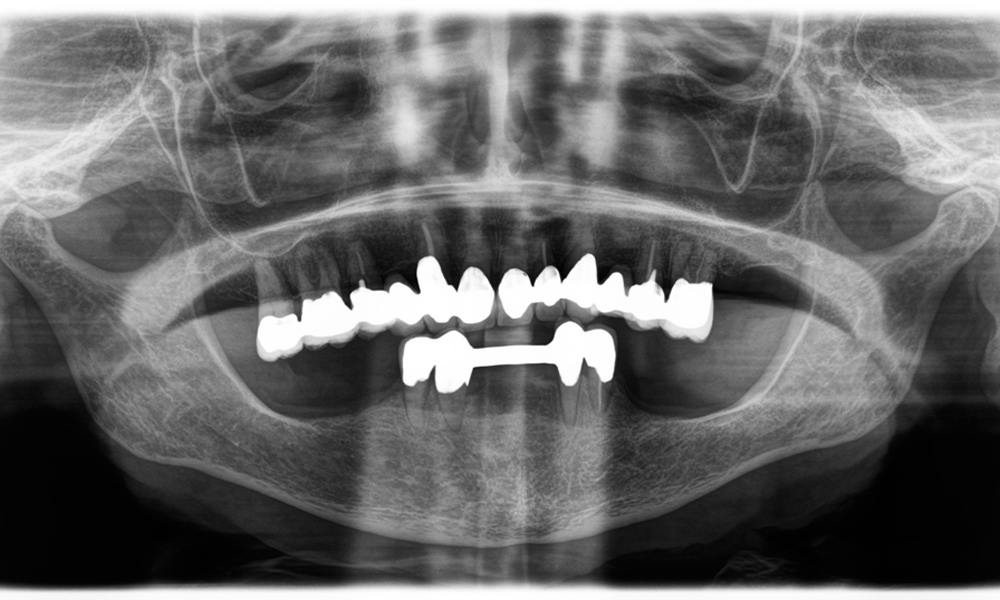

Dr Wolfgang Tautschnig, a dentist with extensive experience from Salzburg, has applied and assessed the Synea Power Edition over several months in a range of clinical scenarios, particularly in the removal of zirconia crowns and the processing of base metal alloys. In one specific case, an 81-year-old patient presented seeking aesthetic improvement of her 40-year-old PFM (porcelain-fused-to-metal) crowns. The existing restorations no longer met her expectations in terms of appearance.

The challenge was to remove twelve splinted crowns made of a base metal alloy without damaging the underlying abutment teeth. The handpiece was used to precisely section the ceramic layers and divide the metal framework using a carbide bur, enabling minimally traumatic crown removal. Within just 30 minutes, the old restorations were removed, allowing for the preparation of a new prosthesis, comprising full-contour zirconia in the posterior region and veneered crowns anteriorly. The result was a complete restoration that delivered both functional and aesthetic success (see Fig. 1).